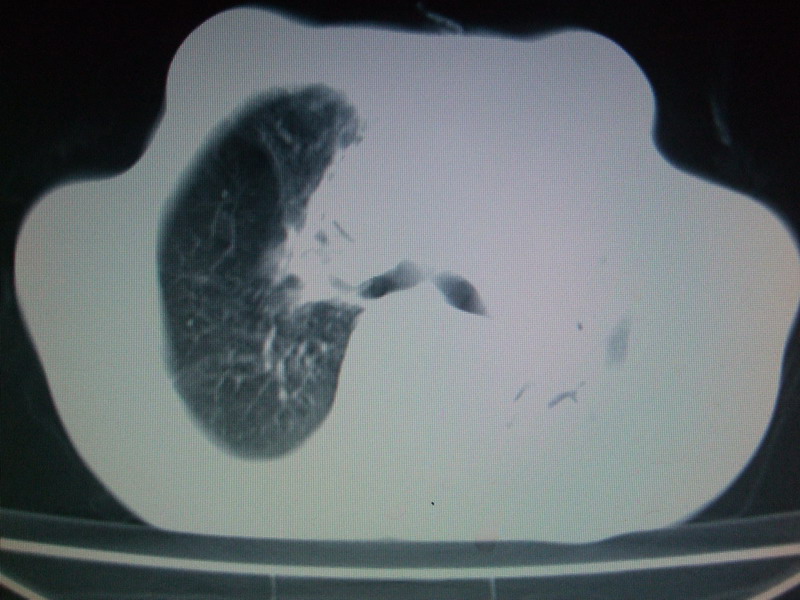

男  70岁,发烧咳嗽4天。盗汗,消瘦。无痰中带血丝,以前有肺tb病史,ct见,双肺tb,左侧胸廓塌陷,左胸膜肥厚粘连。纵隔移位,右侧胸腔积液,大家说说那个心影前左肺舌叶除了肺大炮还有炎症还是干酪性肺炎?有占位吗?我看纵隔淋巴结也大。

1)两肺继发性肺结核并左肺上叶肺不张,支气管扩张。2)双侧胸膜炎(胸膜增厚+少量胸腔积液)。

双肺继发性肺结核伴部分左肺毁损!

双肺继发性肺结核伴部分左肺毁损。